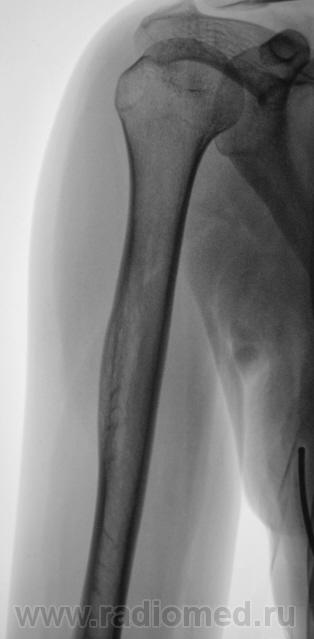

а как на счет левой плечевой кости? все же должно быть в сравнении. и вопросов буде гараздо меньше.

Извольте.

Анатолий Шумаков , в чем отличие правой плечевой кости от левой?

Различий не увидел... Все в пределах нормы.

На снимках справа латерально вроде как прослеживается "мягкотканный компонент". На левой такого нет. А может просто справа мышцы плотнее и накладываются друг на друга, т.к правша?